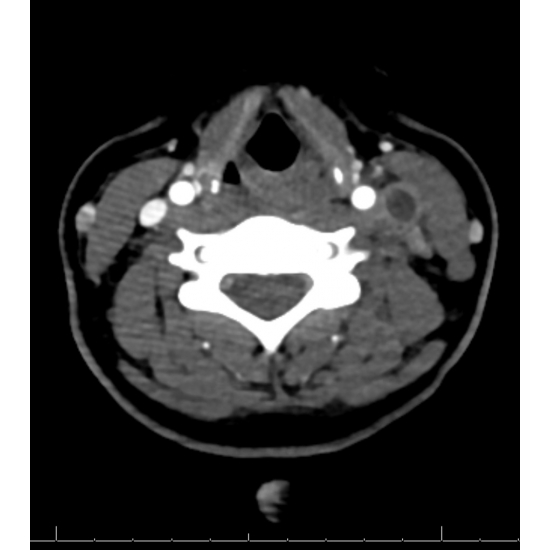

Two days later, she underwent a CT Angiogram of the neck: With mild to moderate left submandibular adenopathy. Occlusive thrombus within left internal jugular vein from C3 level down to the thoracic inlet, involving a 9 cm long segment, compared to the reported 3.1 cm long segment on the duplex sonography. Case Photo #6 and Case Photo #7